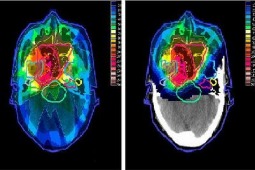

Journal of Contemporary Brachytherapy